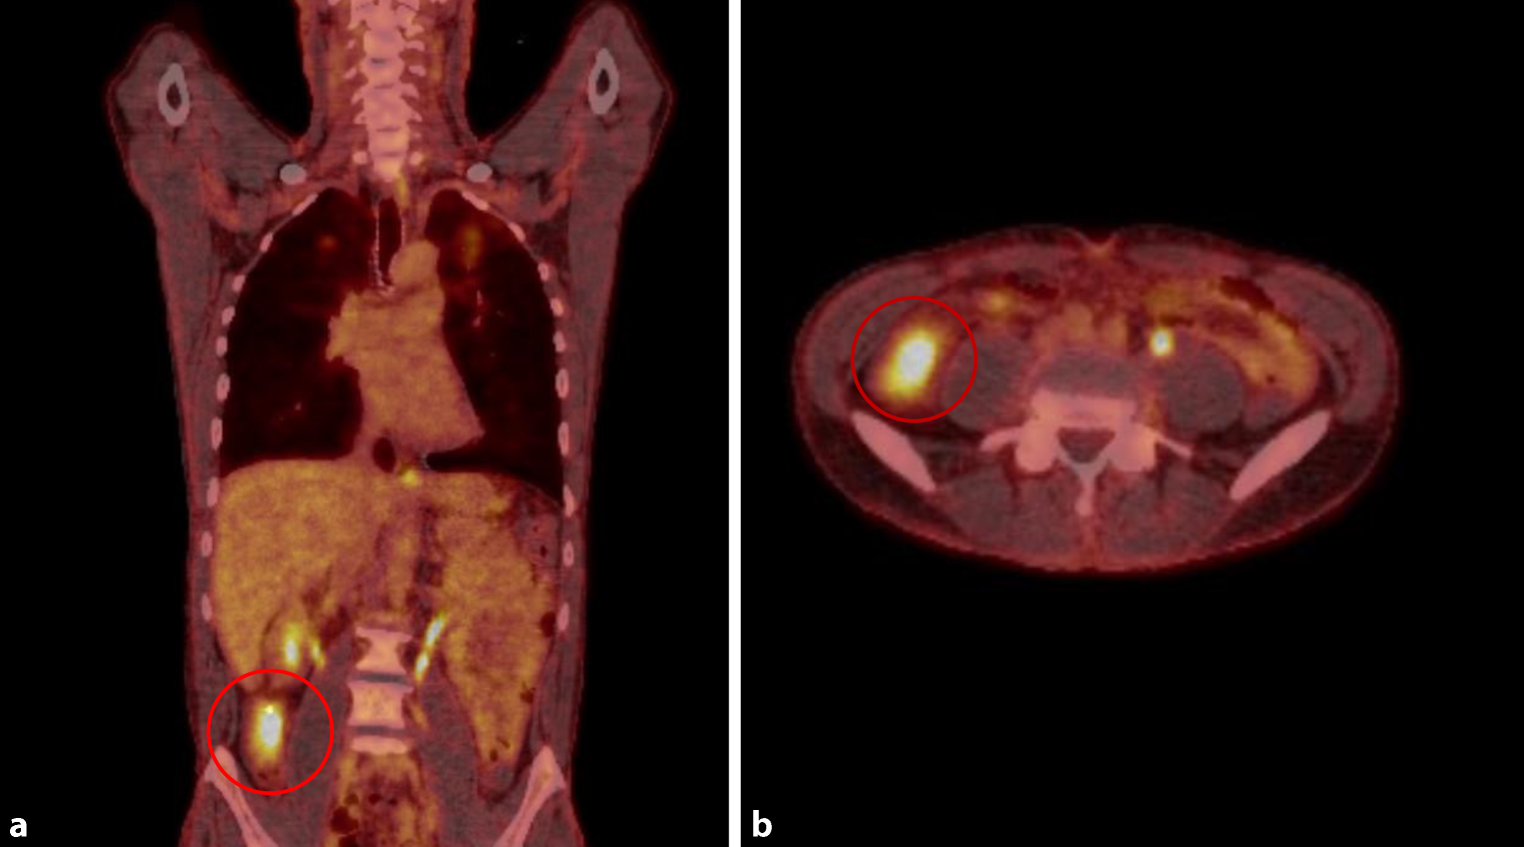

Fig. 4

PET CT scan images of coronal (a) and axial (b) planes showing high metabolic activity in the pulmonary lesions in the left upper lung lobe (red circles) with a maximum standardized uptake value (SUVmax) of 4.0–6.4. The high metabolic activity in the abdomen is a normal finding and represents the kidneys

Antimycobacterial therapy was initiated including isoniazid (H) 300 mg once daily (od), rifampicin (R) 600 mg od, pyrazinamide (Z) 1500 mg od (25 mg/kg body weight) and ethambutol (E) 1000 mg od (15 mg/kg body weight). To rule out involvement of other organs a whole body positron emission tomography/computed tomography (PET-CT) scan with F‑18 fluorodeoxyglucose ([18F]FDG; Siemens Biograph 40, Siemens Healthcare AG, Lausanne, Switzerland) was performed showing increased metabolic activity in the apical regions of both upper lung lobes as well as in the cecum compatible with the tumor mass (Fig. 4 and 5). Other organs did not show any pathological tracer uptake. Contrast magnetic resonance imaging scan (Magnetom Skyra, Siemens Healthcare AG, Lausanne, Switzerland) of the brain showed no evidence of cerebral involvement.